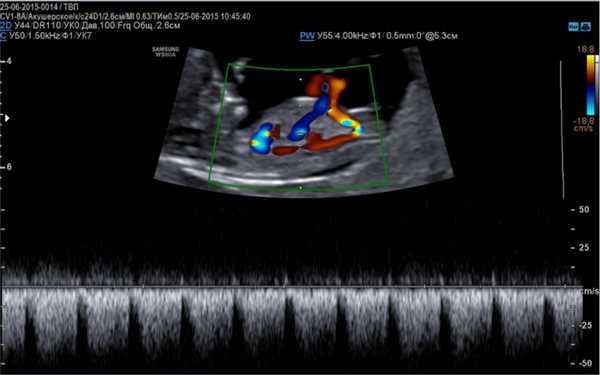

Основой для качественной диагностики является наличие программы, позволяющей определить функциональное состояние сердечно-сосудистой системы на приборе, оснащенным специальным датчиком, имеющим частоту сканирования не менее 5 МГц, а также цветное картирование системы кровообращения и доплер.

- Доплер эхокардиография, более расширенная методика, определяющая гемодинамику, ритмичность и сократительную способность сердца, направленность тока крови по сосудам.

Данные виды исследования также позволяют оценить количество циркулирующей крови, степень сужения артерий, минутный выброс, что является важным диагностическим критерием в диагностике патологий сердца.

Сделать эхо кг можно с помощью цветного аппарата ультразвуковой диагностики и прибором для допплерографии. На ранних сроках вынашивания ребенка применяется вагинальный метод исследования матки. Длительность процедуры составляет около 40-45 минут, однако при подозрении на патологию диагностика может несколько продлиться.

Метод цветного картирования (ЦДК) - это очень эффективное исследование, позволяющие произвести оценку состояния не только сосудов, но и выявить локализацию тромбов, атеросклеротических бляшек, а также аневризму аорты. Интерпретация данных помогает определить специалисту характер новообразования и темп его развития.

На сегодняшний день наиболее широко применяемым исследованием при помощи допплера является тканевая методика. Данный метод оптимизирован для изучения не только направления кровотока, но и визуализации движений сердечных тканей. В ходе допплеровского анализа происходит окрашивание миокарда в различные цвета в соответствии со скоростью и направленностью кровяного потока. Технику применяют для выявления локализованных изменений в сократительной функции миокарда. Данные, получаемые в ходе анализа, регистрируются в виде графика, отображающего зависимость скорости от времени.